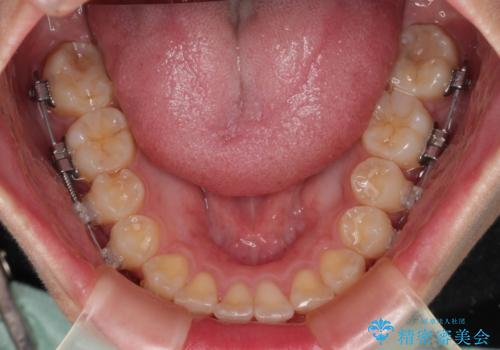

- 矯正装置

- 審美装置

- デコボコを気にして来院された患者様です。

インビザラインでもワイヤー装置でも対応可能でしたが、自己管理の煩わしさの観点から、楽して治療のできるワイヤー装置を選択されました。

抜歯するほどではないものの、やや口元の突出感が気になっていたので、補助装置により上顎臼歯を後方に移動させることで、突出感改善を図ることとしました。